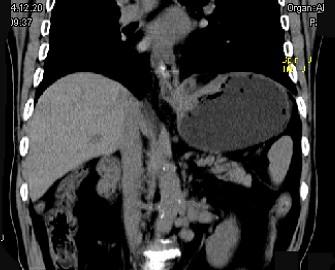

问题 男,75岁,吞咽有梗阻感,消瘦、乏力、中上腹痛,影像检查如图,最可能的诊断是 ( )

选项 A.食管癌 B.胃窦癌 C.贲门癌 D.慢性胃炎 E.胃淋巴瘤

答案 C